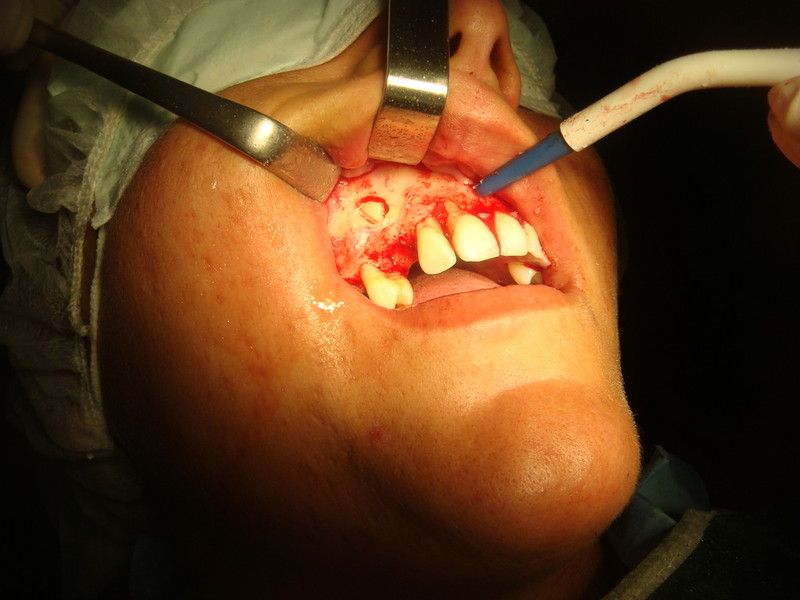

Implantologia avanzata con contestuale rimozione impianti e cisti

Video di una Parte dell'intervento in cui si puo' vedere la comunicazione tra impianti rimossi e pavimento nasale.